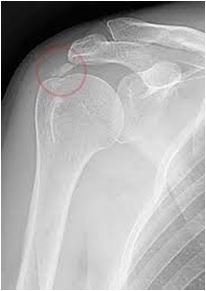

• Πως γίνεται η διάγνωση της ασβεστοποίησης του ώμου;

Η διάγνωση, γίνεται κλινικά και επιβεβαιώνεται με ακτινολογικό έλεγχο, ενώ σημαντικές πληροφορίες προσφέρουν τόσο το υπερηχογράφημα, όσο

και η μαγνητική τομογραφία (MRI) για ανακάλυψη συνοδών βλαβών του ώμου όπως εκφυλίσεις και ρήξεις τενόντων.